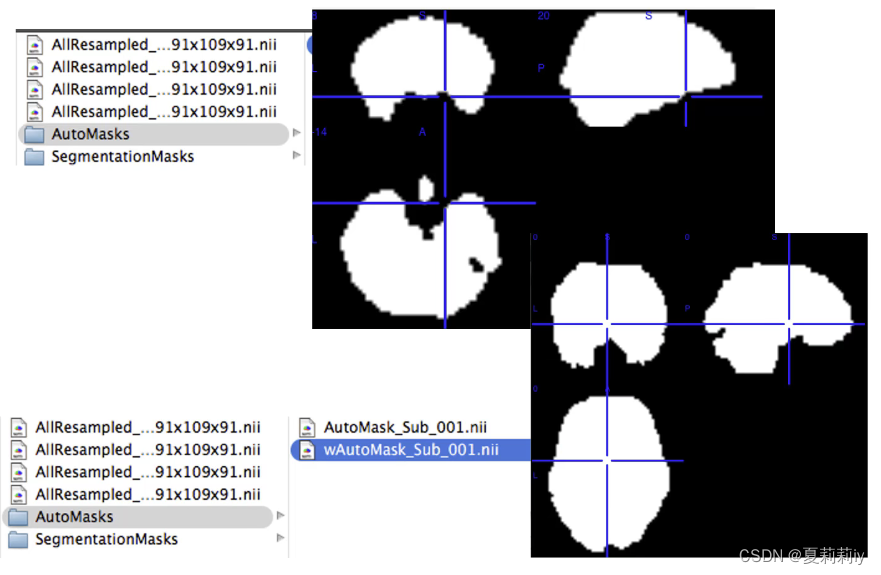

(6)Generate Group Masks

①wAutoMask是MI空间,且根据它可以生成GroupMask

②可以在这个文件中输入值,此例为要求90%的被试都cover这个voxel才进入GroupMask(即进入统计分析)